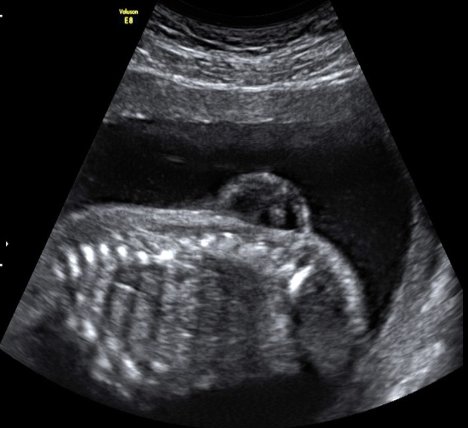

a fetus has pleural effusion, anasarca [skin edema >5mm], and an enlarged liver. which is most likely cause?

.

a) maternal HTN

b) erythroblastosis fetalis

c) ovarian vein thrombosis

d) maternal diabetes